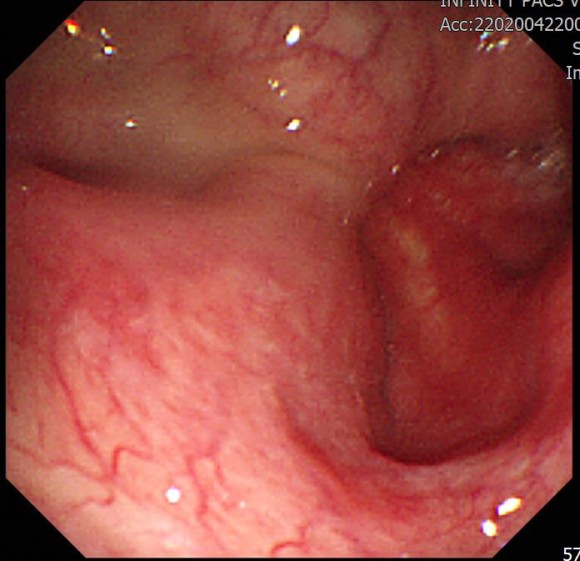

내시경 검사에서 위에는 별 이상이 없었고 식도 하부에 계실이 보였다. 역류성 식도곰은 분명하지 않았다. 이 사진은 어르신이라 코로 들어가는 경비 내시경을 넣어 관찰한 소견이다.

이 분은 딸꾹질과 역류성 식도 질환을 고려해 강력한 위산 억제제를 투여하고 1주일 후에 본 내시경 사진이다.

덧붙여서 역류성 식도염은 내시경 소견으로 위식도 접합부에 염증 소견이 확실하면 붙이는 진단이다. 같은 증상은 있지만 내시경 검사 소견은 명확하지 않으며 같은 치료로 증상이 가라앉으면 광범위한 진단으로 역류성 식도 질환이라고 한다.